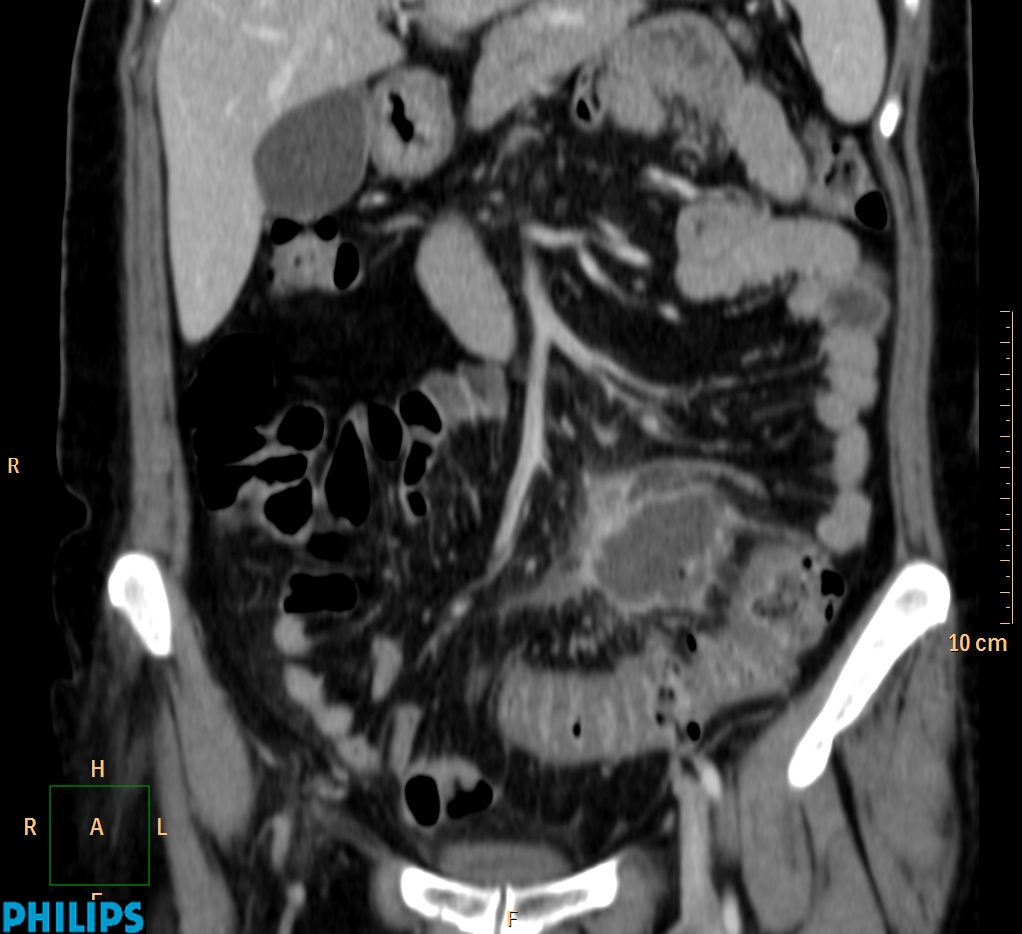

ΕΚΚΟΛΠΩΜΑΤΑ ΠΑΧΕΟΣ ΕΝΤΕΡΟΥ Posted by ΙΠΠΟΚΡΑΤΕΙΟ ΙΩΑΝΝΙΝΩΝ | Dec 16, 2020 | ΠΕΠΤΙΚΟ | 0 ΚΛΙΝΙΚΑ ΣΤΟΙΧΕΙΑ – ΙΣΤΟΡΙΚΟ υποτροπιάζοντες επαναλαμβανόμενοι πυρετοί κυρίως απογευματινές ώρες ΕΡΓΑΣΤΗΡΙΑΚΟΣ ΕΛΕΓΧΟΣ ΑΠΕΙΚΟΝΙΣΤΙΚΟΣ ΕΛΕΓΧΟΣ διακρίνονται τα αποστήματα στην ελάσσονα πύελο, καθώς και εκκολπώματα με εικόνα πάχυνσης του τοιχώματος του σιγμοειδούς ΣΥΖΗΤΗΣΗ